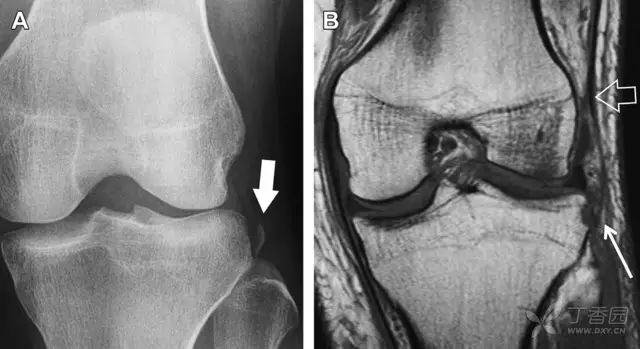

膝关节撕脱骨折和压缩骨折常伴发于韧带损伤,若想准确诊断,在了解这些骨折高发部位的同时,还需仔细认真地阅片,否则有些骨折就被漏诊了。

前交叉韧带撕脱骨折常发生在胫骨髁间嵴(图 1)。这种骨折在青少年中常见,但在成年人中也并不像大家想象的那么少见。

图 1 摩托车事故患者前交叉韧带撕脱性骨折

A 正位片示胫骨髁间嵴底部骨折(箭头),注意别把这个骨折碎片错认为关节内结构。B 侧位片示胫骨上方可见一细长型骨折碎片(椭圆)。C MRI 矢状位 T2 加权像示前交叉韧带附着于撕脱的骨折碎片上(箭头),注意周围存在骨髓水肿和积脂血征(空箭头)。

图 2 扭伤后的股骨外侧髁凹陷征

A 侧位片示股骨外侧髁凹陷。B MRI 矢状位 T2 加权像示股骨外侧髁及胫骨后外侧骨挫伤(空箭头)。胫骨近端随着后交叉韧带撕裂发生移位,露出外侧半月板的后角(弧形箭头)。

胫骨后外侧小片骨皮质的压缩性骨折,可能是旋转移位损伤的唯一证据(图 3)。这种骨折在常规膝关节平片很难发现,若怀疑存在骨折,行下肢内旋斜位片检查可诊断。

图 3 胫骨后外侧碎片骨折

A 正位片示胫骨后外侧处可见一压缩骨折的小碎片(方框)。这是胫骨撞击股骨外侧髁旋转移位时所致。B 另一位患者的 MRI 矢状位 T1 加权像示胫骨后外侧骨折碎片(箭头)。

Segond 骨折是发生在胫骨平台外侧的垂直撕脱性骨折(图 4)。这种骨折在前后位 X 线片上显示最佳。

屈曲位时膝关节受到内旋暴力作用,导致皮质骨撕脱性骨折,这种骨折常发生在运动员身上。常引起股骨内髁和胫骨平台后内侧骨挫伤,75%~100% 的患者伴前交叉韧带断裂,33% 的患者伴外侧半月板损伤。

图 4 一位足球运动员的 Segond 骨折

A 正位片示关节线下方胫骨外侧皮质撕脱(箭头)。B MRI 冠状位 T1 加权像示附着于髂胫带的骨折碎片(空箭头)。

胫骨平台内侧皮质骨撕脱性骨折,被称为内侧 Segond 骨折或反向 Segond 骨折(图 5)。这种骨折的旋转机制与 Segond 骨折相反,该骨折与后交叉韧带断裂及内侧半月板损伤相关。

图 5 一位足球运动员的反向 Segond 骨折

A 正位片示关节线处的胫骨内侧见一细小骨折片(箭头)。B MRI 冠状位 T1 加权像示骨折片出现在内侧副韧带关节囊附着处(方框)。

为胫骨前内侧受到直接暴力作用,发生在腓骨茎突的横形骨折,可表现为弓形信号(图 6)。可伴发前交叉韧带或后交叉韧带的断裂。如果弓形信号被忽视或未处理,前交叉韧带的重建将失败。

图 6 跌倒后发生腓骨茎突骨折

A MRI 冠状位 T1 加权像示腓骨茎突撕脱性骨折(箭头)。弓状韧带附着于骨折碎片,而联合腱绕过外侧附着于其上。B 正位片见横形骨折线(箭头)。

约 6% 的后交叉韧带断裂与撕脱性骨折有关。X 线片特征表现为膝关节侧位片上可见大小不等的三角形骨折碎片移位到关节内(图 7)。

图 7 车祸后的后交叉韧带撕脱骨折

A 侧位片示后关节间隙见一移位的三角形骨折碎片(箭头)。B 矢状位 MRI 图像示骨折碎片(实箭头)附着于后交叉韧带上(空箭头)。

膝关节外侧由髂胫束、股二头肌和肌腱、外侧关节囊韧带及外侧副韧带组成。外侧副韧带对抗过度内旋暴力,维持膝关节稳定。当内旋暴力足够大时,韧带断裂或腓骨头撕脱性骨折就发生了。在 X 线片上,骨折线垂直于股骨头外侧(图 8)。

图 8 过度伸展引起的腓骨头撕脱性骨折

A 侧位片示腓骨头外侧的垂直骨折(箭头)。B MRI 冠状位 T1 加权像示骨折碎片同时附着于外侧副韧带(箭头)和弓状韧带上(弧形箭头)。